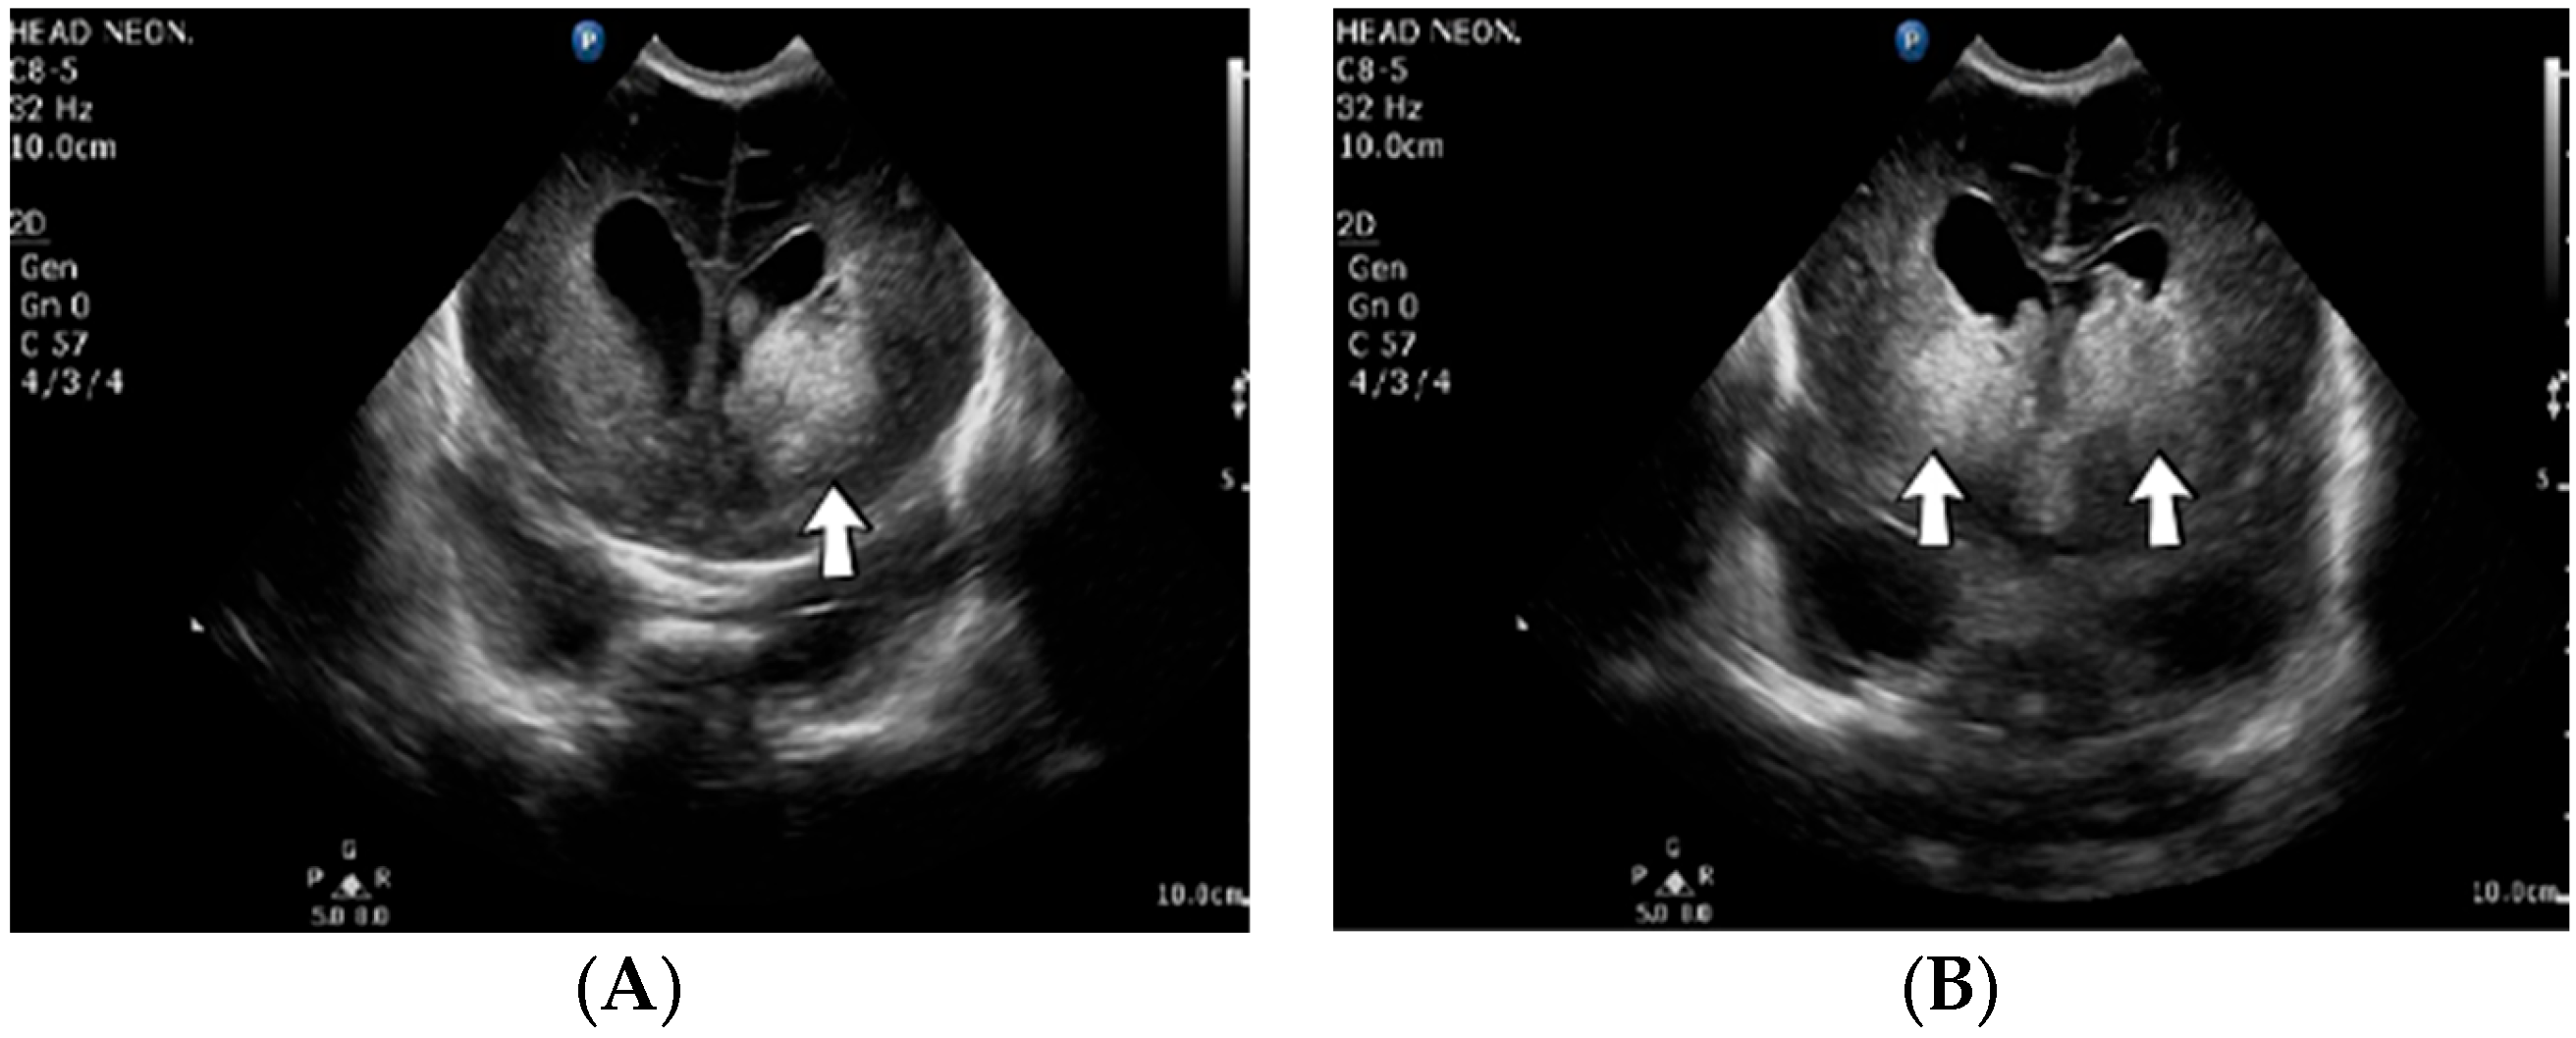

A 2-week-old male neonate (36 weeks, 2.99 kg), delivered by emergency cesarean section due to abnormal cardiotocography and severe oligohydramnios, with true umbilical cord knot at birth, presented with left intraventricular and intraparenchymal hemorrhage revealed from the brain ultrasound performed at 8 h of life. Myoclonic seizures appeared three days after admission, progressing to generalized tonic–clonic seizures. An ultrasound of the brain was performed, which indicated new bleeding of the bilateral basal ganglia (Figure 4).

Figure 4.

Case no. 4. Left intraparenchymal hemorrhage (A) from admission and bilateral basal ganglia hemorrhage three days after the admission (B) on brain ultrasound.

Genetic testing confirmed inherited thrombophilia, with positive MTHFR A1298C and MTHFR C677T heterozygous gene mutations and Antithrombin, Protein S, and Protein C deficiencies. Normal homocysteine levels were detected. There was a positive family history of maternal thrombophilia, treated with enoxaparin and acetylsalicylic acid during pregnancy.